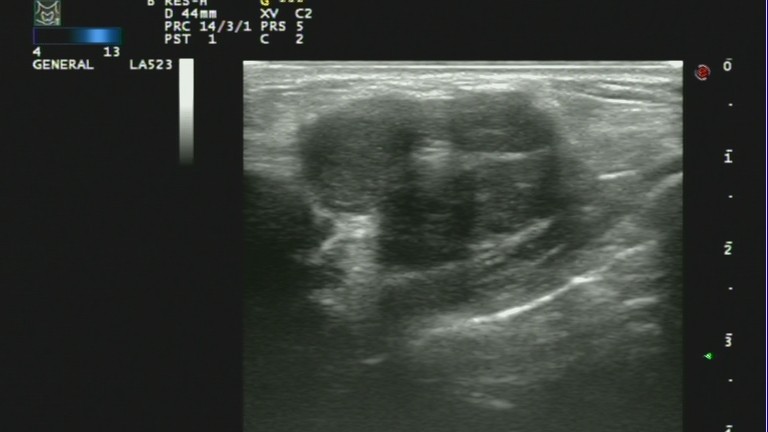

1、肿块多呈不均质的低回声,没有包膜,后方回声可衰减。

2、肿块不规则,会有分叶情况,典型的有“蟹足状”。